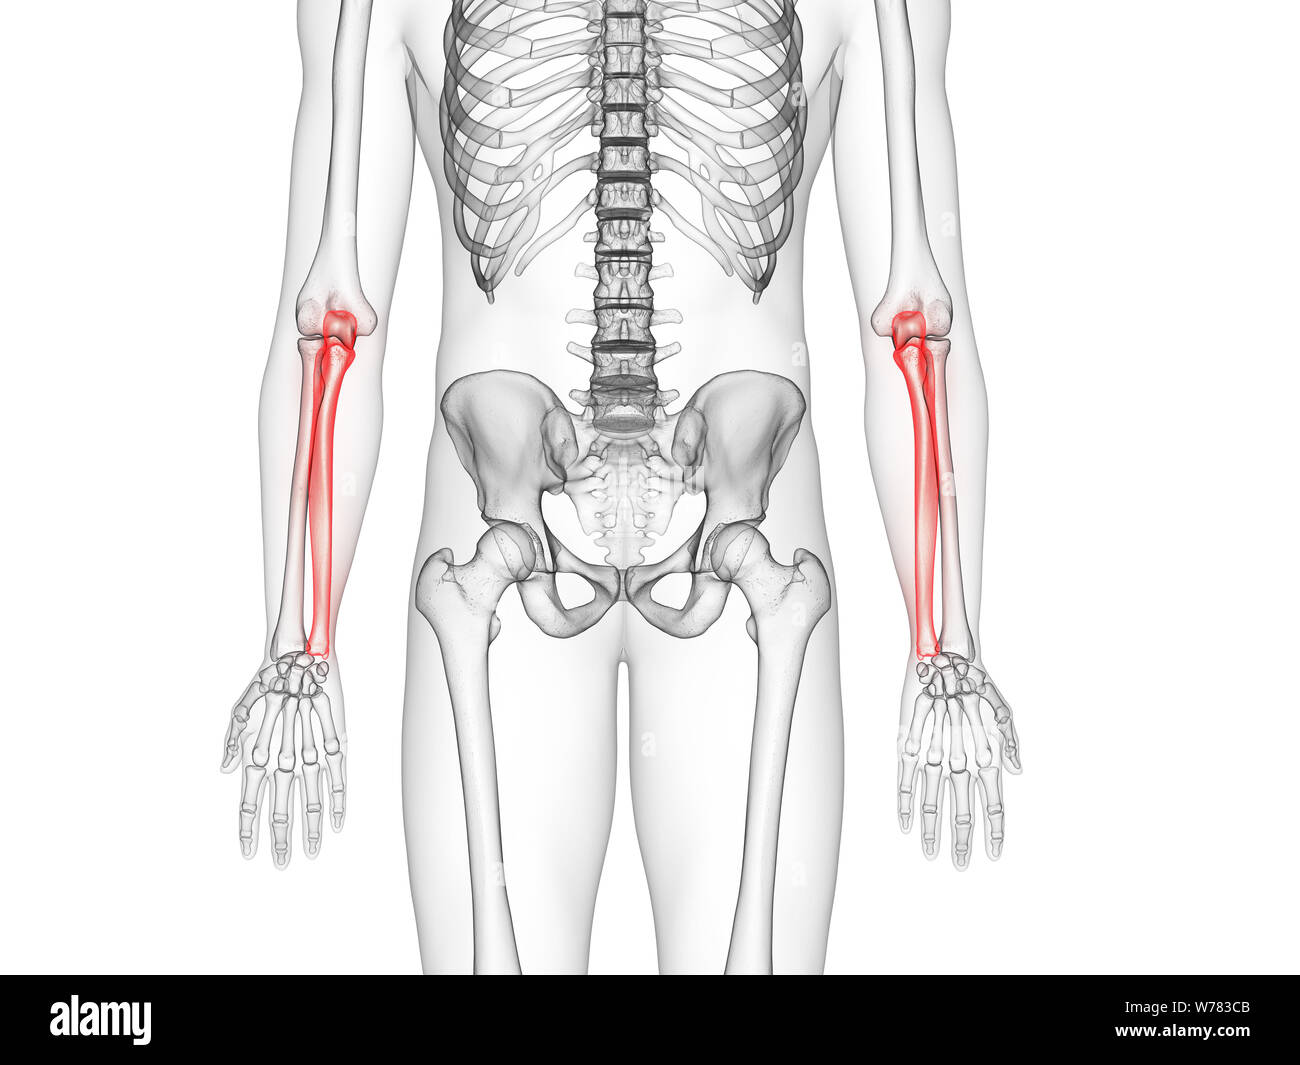

Human Skeleton Anatomy Ulna Bone 3D Rendering Stock Illustration Pain On Ulna Bone ulnar wrist pain occurs on the side of your wrist opposite your thumb. ulnar wrist pain (pain on the pinkie side of the wrist) is very common. The pain can become severe enough to. the objectives of this article are to provide an overview of the most common problems that are encountered in. It can result from. Pain On Ulna Bone.

From www.alamy.com

3d rendered medically accurate illustration of the ulna bone Stock Pain On Ulna Bone ulnar wrist pain, while at rest or with movement, is a common sign of many different injuries and medical. It can result from injury to bones, cartilage, ligaments or tendons. ulnar wrist pain is so common that it can sometimes be difficult to determine the exact cause. the most common issues that affect the ulna are fractures,. Pain On Ulna Bone.